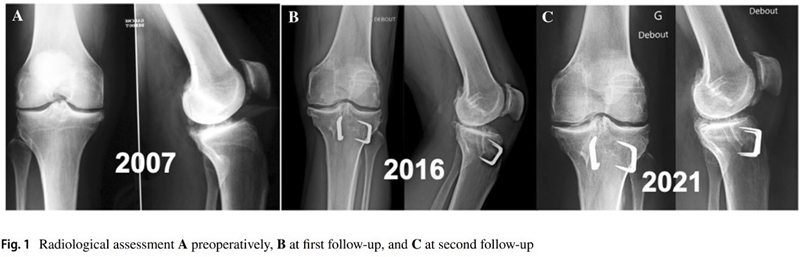

Anouk等人分析ACLR翻修联合胫骨去屈曲截骨术(TDO)的9名患者数据,指出在术后7-15年与术后2-8年随访结果相比,患者的临床评分保持或改善,没有再撕裂或再次手术的情况。证实TDO可以防止ACL移植物再撕裂,在进行ACLR时,无论是翻修还是初次手术,都应考虑矫正过度的胫骨后倾[6]。

图4